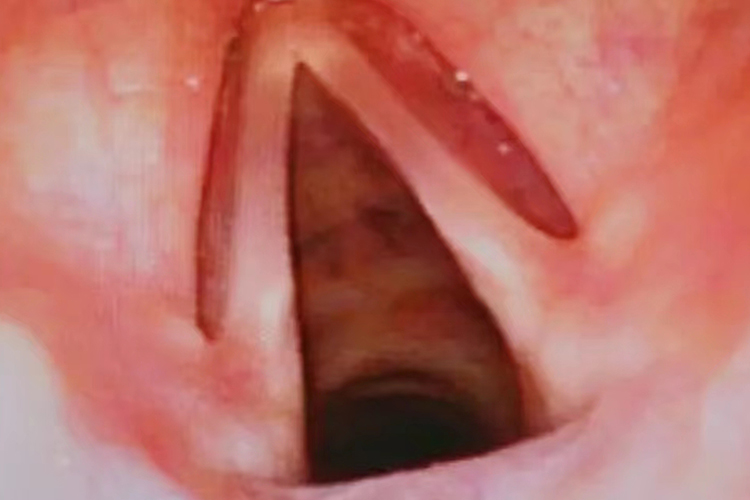

构成:喉腔上界为喉入口,由会厌游离缘、两侧构状会厌襞和构区以及杓间区构成;其下界是环状软骨下缘。喉腔侧壁上有两对软组织隆起,上一对名为室带,又称假声带,下一对名为声带,两侧声带之间称为声门裂。室带与声带之间的间隙名为喉室。以声带为界可将喉腔分为声门上区、声门区和声门下区。